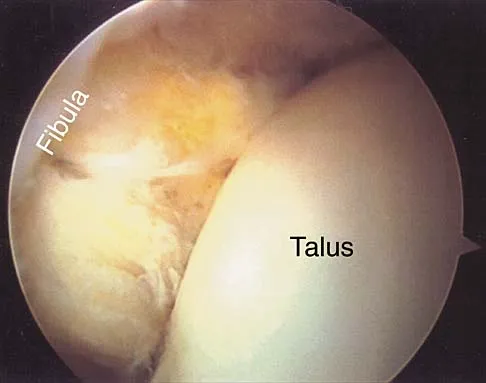

A cord-like middle glenohumeral ligament and absent anterosuperior labrum complex can be a normal anatomic capsulolabral variant. If this normal variation is repaired during arthroscopy, it will cause